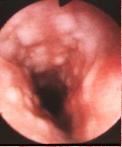

Image endoscopie intra oesophagien

mulptiple de papilomes de l'oesophage . Reaction

inflamatoire legere |